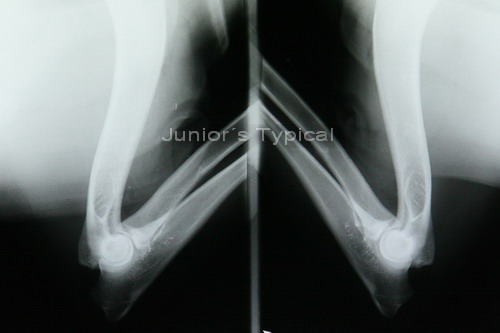

![]() |

| Lagerung der Ellenbogen, gestreckt. |

| Aufnahme dazu. |